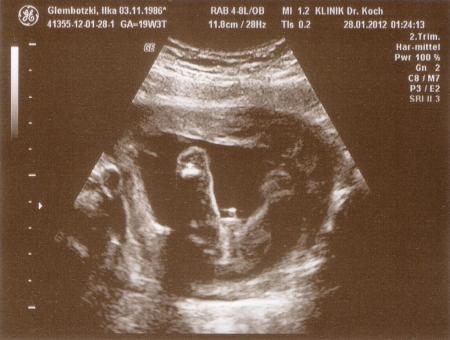

Nun haben wir die Bilder von Freitag mal eingscannt ;-) Das ist also bei 19+2 1. Bild = Profil 2. Bild = Popo zum Schallkopf, Beine in der Luft gespreizt und Prachtstück mittig platziert *lach* (das eindeutige Outing)

Sehr schöne Bilder und ein eindeutiges Outing

also eindeutiger gehts echt nicht man sieht das richtig gut... musst dich bei dem anblick ja halb tot gelacht haben... war dein Menne dabei??? den muss das auch amüsiert haben!!! Hoffe auch auf ein derart eindeutiges Outing!!! LG sabby 18+4

Nein wie niedlich! Schaut aus als wollte er sagen:" Guck mal Mama ich bin ein Junge!" :o)